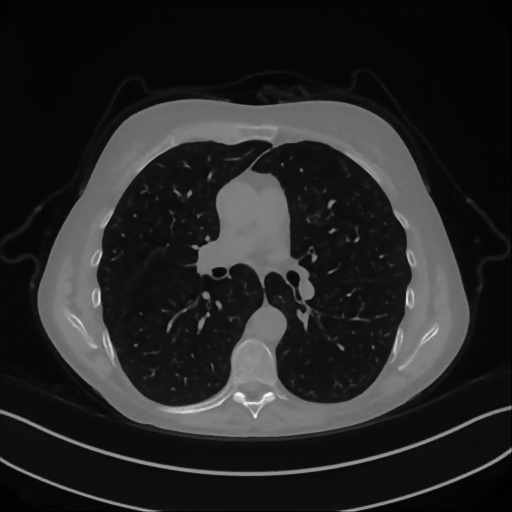

Here we present the results of RISING applied to the Mayo data set introduced in paragraph 4.1. As previously mentioned, we consider two sparse-view CT geometries, namely P360,360subscript𝑃360360P_{360,360} and P360,180subscript𝑃360180P_{360,180}. In Figure 4 we report the results for the P360,360subscript𝑃360360P_{360,360} protocol, achieved on one image of our test set. The top-left image represents the xRIS=x(15)subscript𝑥𝑅𝐼𝑆superscript𝑥15x_{RIS}=x^{(15)} reconstruction. Even if only a small number of iterations are performed, the main structures of the abdomen are visible; however, the image is still blurry. In the xISsubscript𝑥𝐼𝑆x_{IS} image, shown in the upper-right corner, we notice that the TV regularizer has acted to totally eliminate the artifacts and noise, improving the uniformity of the image in the inner structures. When compared to the ground-truth solution in Figure 2, the contours of the details in xISsubscript𝑥𝐼𝑆x_{IS} appear slightly jagged, differently from xGTsubscript𝑥𝐺𝑇x_{GT} where they are neat but, usually, corrupted by artifacts. The bottom row of Figure 4 shows the two xLPPsubscript𝑥𝐿𝑃𝑃x_{LPP} and xINGsubscript𝑥𝐼𝑁𝐺x_{ING} images, respectively from left to right. It is evident that xLPPsubscript𝑥𝐿𝑃𝑃x_{LPP} has retrieved many details but it presents noisy components, reflecting the features of its target image xGTsubscript𝑥𝐺𝑇x_{GT}. Our solution xINGsubscript𝑥𝐼𝑁𝐺x_{ING} is less corrupted, since the low-contrast regions are correctly preserved and the noise is not visible. These observations are confirmed by Figure 5, which plots the intensity profiles taken over the red line in the second crop (Figure 2). In our approach (on the right) the CNN has accurately learnt the f𝑓f map of (8) and the xINGsubscript𝑥𝐼𝑁𝐺x_{ING} red profile mostly overlaps the black one. On the contrary, the xLPPsubscript𝑥𝐿𝑃𝑃x_{LPP} profile (on the left) is more distant from its target reference.

Refer to caption

Figure 4: Results on a test image from the Mayo data set, under the P360,360subscript𝑃360360P_{360,360} CT protocol. Top-left: xRISsubscript𝑥𝑅𝐼𝑆x_{RIS}; top-right: xISsubscript𝑥𝐼𝑆x_{IS}; bottom-left: xLPPsubscript𝑥𝐿𝑃𝑃x_{LPP}; bottom-right: xINGsubscript𝑥𝐼𝑁𝐺x_{ING}.